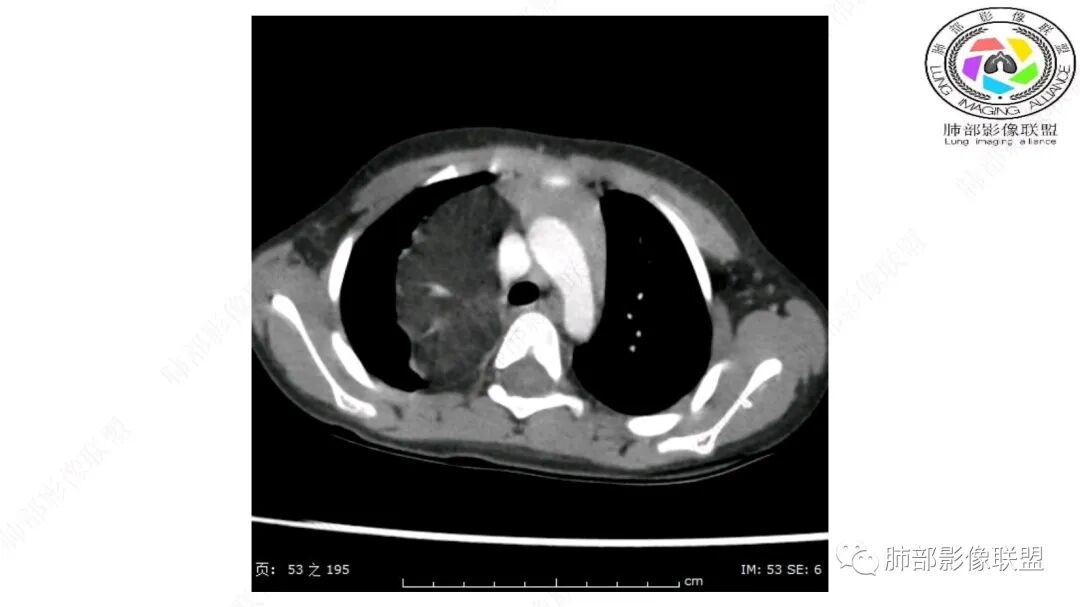

Coke with ice:

跨肺门,包绕肺血管分支,邻近肺组织受压肺不张。

可以看到造影剂进入的丛状结构

密度不均,非纯脂肪成分。斑片状密度略高区域有轻度填充式强化。

婴幼儿,病变较大,跨肺门,分叶,富含纤维或黏液、含成熟脂肪,破坏力弱或无,浸润性生长模式不明显,未见远处转移。

综合:富含成熟脂肪的、可以有丛状结构的,可以有纤维或黏液的良性或低度恶性肿瘤。常见疾病谱:脂肪瘤、神经纤维瘤样错构瘤、冬眠瘤、血管脂肪瘤、髓脂肪瘤、脂肪母细胞瘤、黏液样脂肪肉瘤。

鉴别要点:病变成分不单一,非包绕神经结构、间质血管不显著、婴幼儿,良性或低度恶性。

病灶属于交界区,主体位于肺内,占位效应明显,前方突入胸壁,胸腺受压变形,胸膜显示欠清楚;病灶包绕上叶肺动脉;似乎有体动脉供血。符合肺内的点:包绕上叶肺动脉分支;符合纵隔的点:前方似乎突入胸壁,与胸腺关系比较密切,但是与上腔静脉的关系提示病灶不支持纵隔来源,前纵隔的常规会将上腔静脉受压后移、外移,这是不符合的。

内部血管明显,部分病灶密度增高,单纯脂肪瘤不支持。可惜的是:没有提供CT值:是否强化?如果强化,警惕恶性;胸腺肯定不符合,胸腺会将上腔静脉朝后推移。

脂肪母细胞瘤由成熟程度不同的脂肪组织、纤维间隔、黏液基质、小血管丛等间质成分组成,以脂肪组织与黏液样基质为主,其影像学表现取决于上述组织成分。典型的CT和MRI表现为:前后纵隔均可发生,常见于前纵隔;肿块大小不一,直径多在3cm~7cm,密度均匀,CT值呈水样或脂肪密度,脂肪组织密度或信号为主的肿块,其内密度或信号不均匀,可见粗细不一的分隔影,且有结节、片状影,后者可呈轻中度强化;结节状肿瘤包膜完整;弥漫性者包膜不明显,常呈浸润性生长;周围结构为受压和推移改变,可有少量胸腔积液,淋巴结无增大。